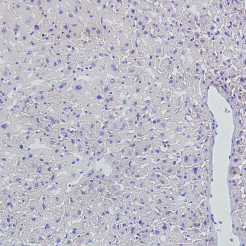

image.pngimage.png

脑组织-尼氏染色-冰冻切片脑组织-尼氏染色-石蜡切片